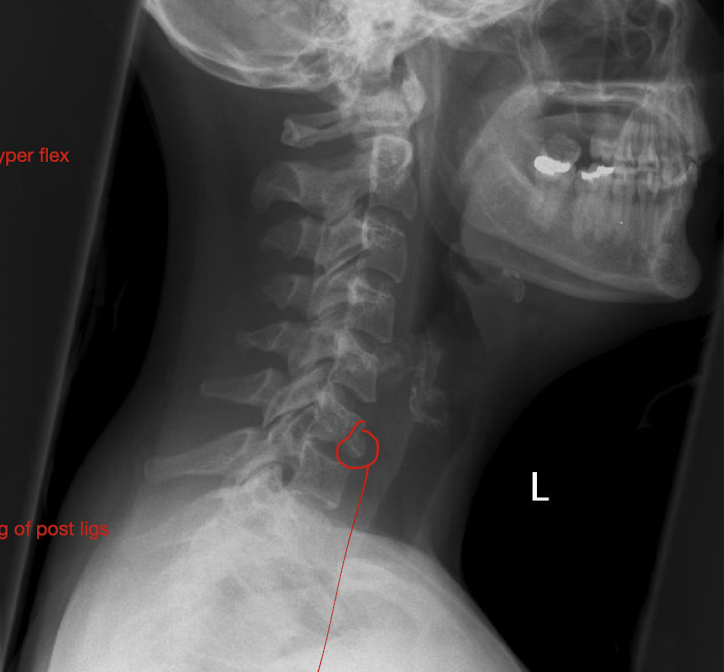

Fracture of C3-C7: Tear Drop Fx

What is this fx known as?

How does it occur?

2

Known as:

Most severe of the Lower C/S Fx (Hyper Flexion)

How:

Separation of a piece of bone from the Anterioinferior border of the vertebral border

Hyperflexion or Hyperextension

Fracture of C3-C7: Tear Drop Fx

How much force causes pieces to rupture off and tearing of post ligs.

Stable or Unstable Injury

Large Force

Unstabble